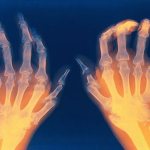

Признаки заболевания проявляются не только физическим состоянием пациента, но и внешне. При осмотре пациента отоларингологом он замечает, что миндалины поменяли свой цвет. Если у пациента наблюдается воспалительный процесс, то гланды становятся ярко красного цвета. Также доктор замечает значительное увеличение миндалин в размерах. По своим размерам они напоминают не зерна миндаля, а грецкие орехи. Для миндалин характерна рыхлость. У большинства пациентов возникают спайки рубцового характера между гландами и дужками неба.

При появлении заболевания доктора могут диагностировать появление желтовато-белого налета и гнойных пробок, для которых характерно наличие неприятного гнилостного запаха.

Если эти симптомы сопровождаются общей слабостью в организме и высокой температурой, то необходимо подозревать гнойное воспаление миндалин. При этом миндалины становятся очагом таких микробов, как: стрептококк, стафилококк и др. С миндалин они распространяются по всему организму и влияют на работу жизненно важных органов, возникают воспалительные процессы, может развиваться простатит, воспаление околоносовых пазух, дисбактериоз. У человека возникает ощущение чужеродного тела в горле.

Если вовремя не начать лечение, то у пациента могут начать развиваться такие осложнения, как: сердечный ревматизм, гломерулонефрит, пролапс сердечных клапанов, паратонзиллярный абсцесс, воспаление легких, снижение слуха, обостренные аллергические реакции.

Возможные осложнения

Лечение воспаления гланд должно производится сразу же после появления первых симптомов. В противном случае у пациентов могут наблюдаться осложнения. Наиболее часто данное заболевание провоцирует ухудшение работоспособности сердца и суставов. В некоторых пациентов наблюдается при несвоевременном лечении ухудшение состояния почек.

Если воспаление гланд постоянно переходит в окружающие ткани, тогда назначается их удаление. Если заболевание имеет гнойный процесс, то он может переходить на сердце и легкие. Это состояние является очень опасным не только для здоровья, но и для жизни пациента.

При переходе гнойного процесса на окружающую ткань у пациентов может наблюдаться гнойный абсцесс.